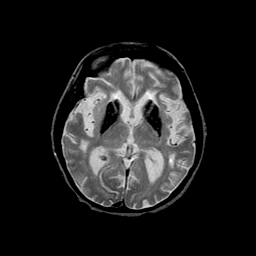

Basal Ganglia Calcification: T2-weighted MR -- Slice #9

[Home][Help][Clinical] Slice 9